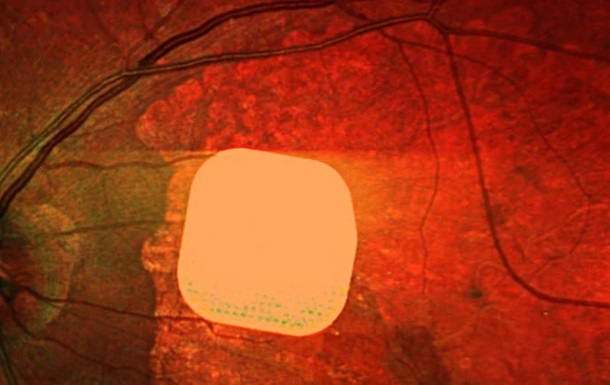

Офтальмологи з лондонської клініки Moorfields Eye Hospital разом із колегами з інших європейських медзакладів випробували надтонкий електронний імплант Prima, який дозволяє частково відновити зір пацієнтам із макулодистрофією – головною причиною втрати зору після 50 років.

Мікрочип розміром лише 2×2 міліметри і завтовшки з половину людської волосини хірургічно встановлюють під сітківку ока. Під час операції, що триває менше двох годин, пацієнту також під’єднують систему окулярів доповненої реальності з камерою і мінікомп’ютером. Камера зчитує навколишнє зображення, перетворює його на інфрачервоний сигнал і передає на мікрочип, який активує клітини сітківки. Потім через зоровий нерв сигнал надходить до мозку, утворюючи візуальне сприйняття.